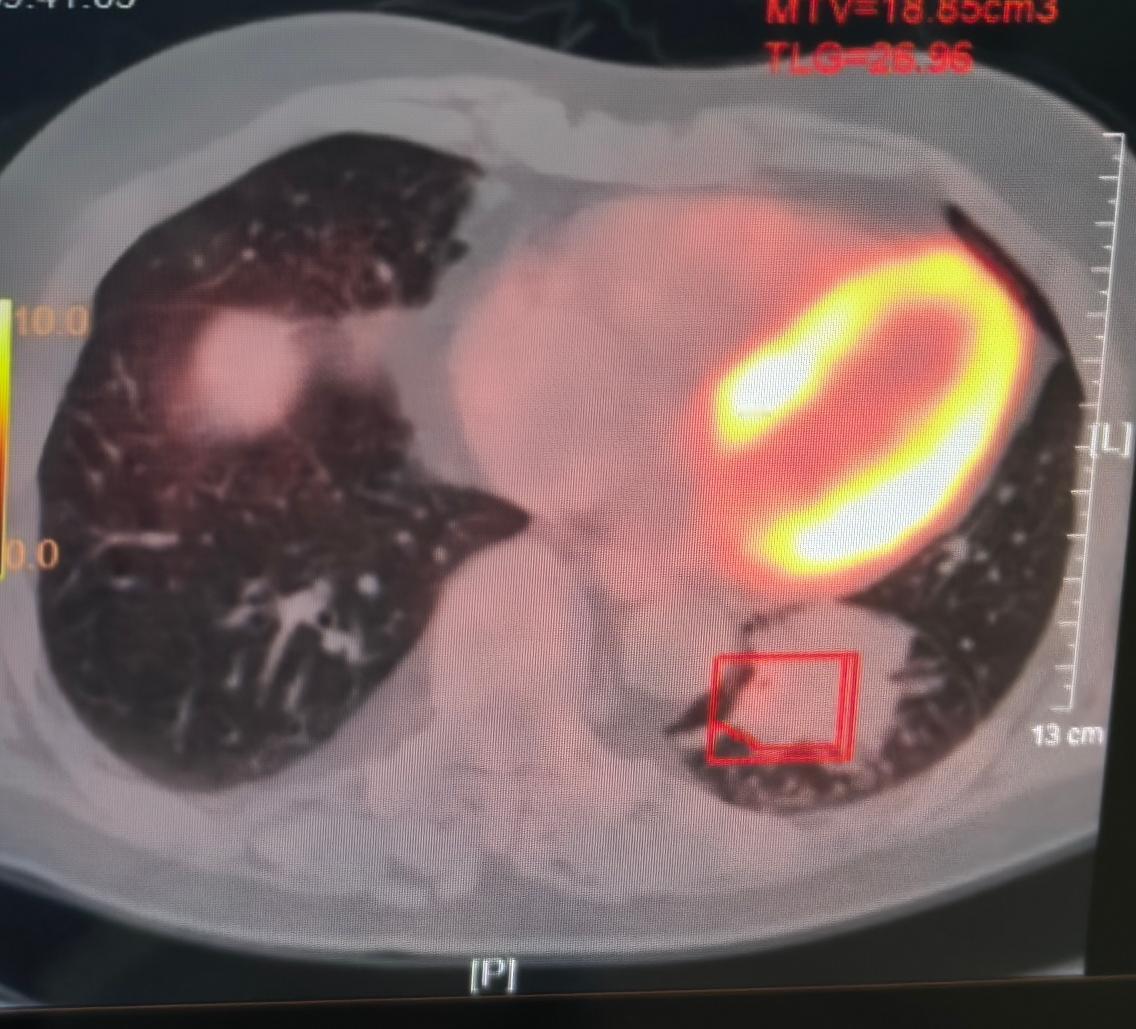

4个疗程结束后复查,肿瘤还有6公分左右,虽然依旧不小,但老人家的精神状态非常好,全身也没有出现转移。我当时就推测,这6公分的肿块里,可能不都是活的肿瘤细胞。

当我把切下来的肿块刨开时,一下子就松了口气——里面大部分都是黄色的炎症坏死组织,也就是说,大部分肿瘤细胞其实已经被消灭了。